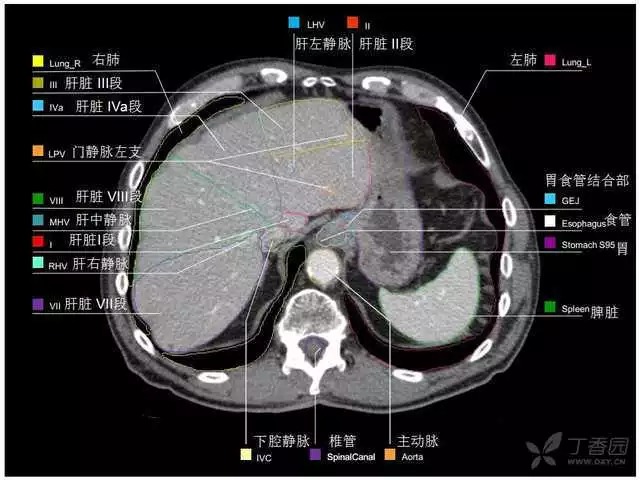

腹部肝脏高清CT断层的图谱

全腹部高清CT图谱,淋巴结彩色图谱,血管解剖图谱大汇总!

肝段,肝内管道的分布规律

美国放射学会ACR官网,对肝脏的区域和节段解剖学概述